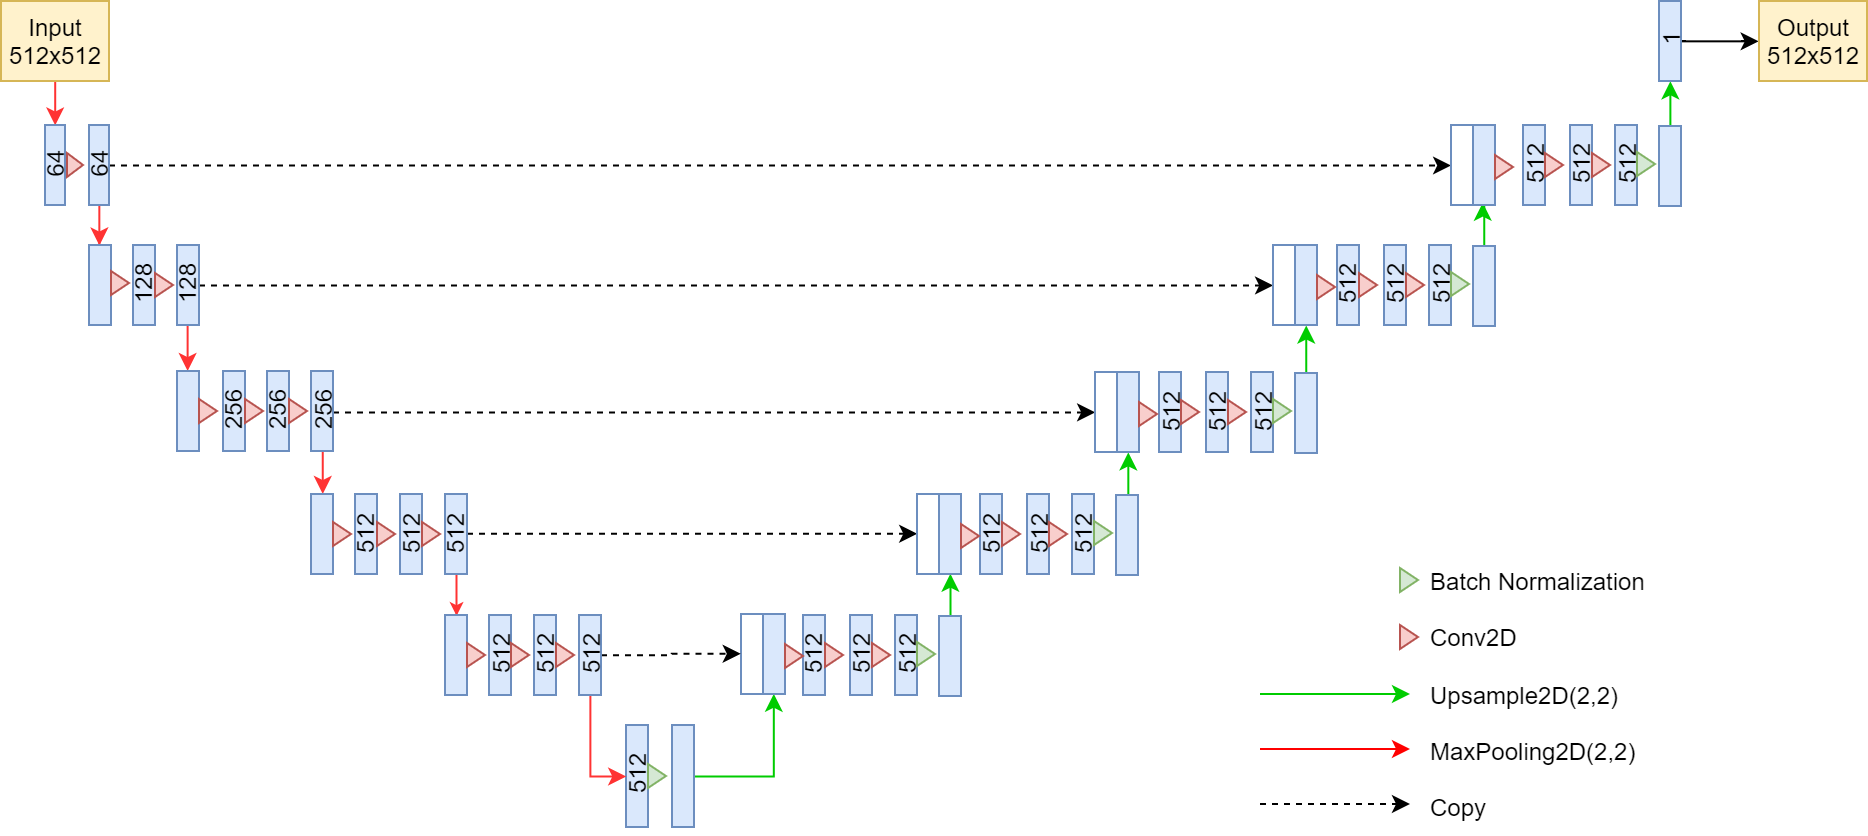

U-Net is a popular biomedical image segmentation network. Similarly to Segnet, U-Net consists of an encoder, using VGG11 architecture [17], and a decoder with upsampling layers. The output of each encoder layer is fed into the corresponding decoder layer by concatenating with the output from the previous decoder layer. We modified U-Net by using VGG16 architecture instead of VGG11. Figure 2 illustrates our model architecture. The input images to our model are 512 by 512 pixels in size.